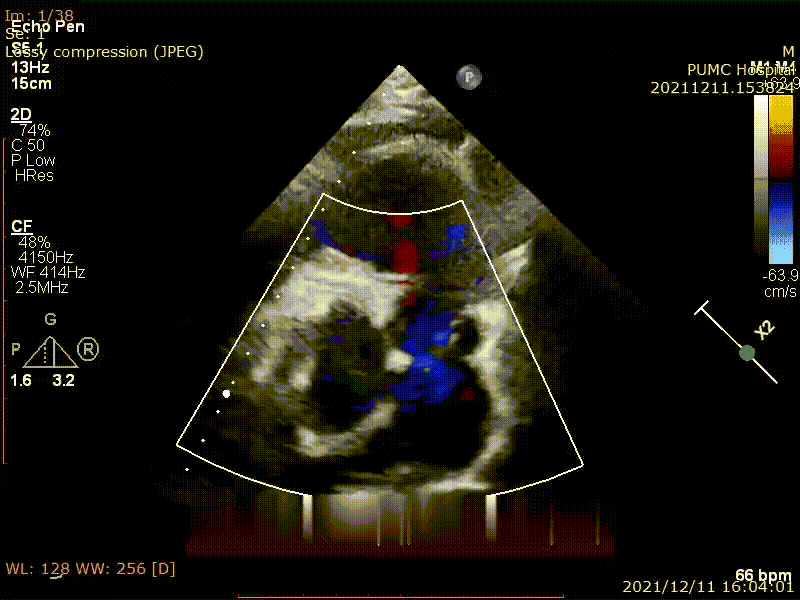

术前超声评估

右心增大(右室横径52mm),主肺动脉增宽(28mm),肺动脉瓣环直径27.9mm,肺动脉瓣环下2cm右心室流出道直径26.9mm,肺动脉瓣环下1cm右心室流出道直径25mm,3D测量右室舒张末期容积160ml,RVEF 50.3%。彩色多谱勒血流显像及频谱多谱勒:肺动脉口前向血流速度增快,CW峰值速度2.8m/s,PGmax 30mmHg,PW测量肺动脉主干峰值流速2.7m/s,肺动脉瓣瓣下2cm右心室流出道峰值流速1.0m/s,余瓣膜血流速度未见明显增快,肺动脉瓣可见大量反流束(反流束宽度/瓣环直径大于50%,PR-PHT 105ms,右肺动脉见舒张期反向血流);三尖瓣可见中量反流束,估测右室收缩压为45mmHg(右心房压力 3mmHg)。

术前超声显示肺动脉瓣大量反流束